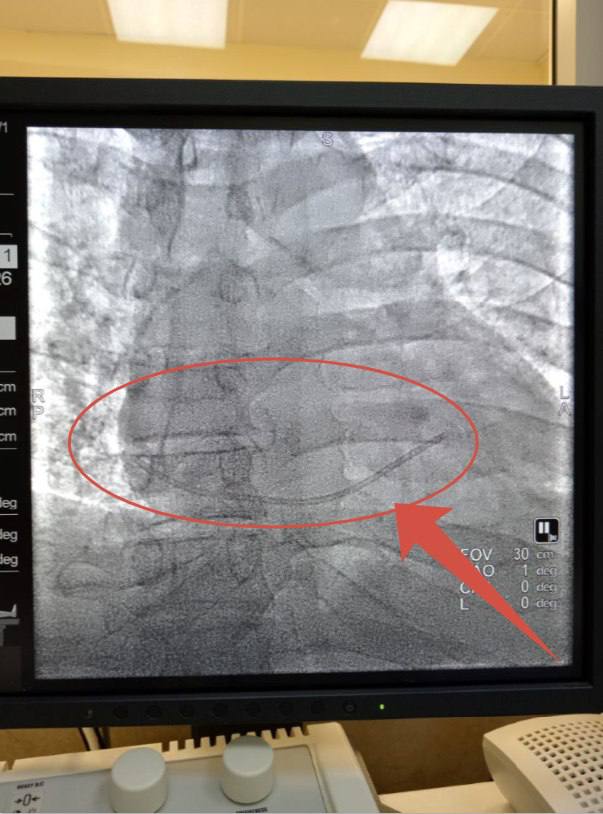

Оторвавшийся катетер попал в сердце 48-летнего мужчины

Кардиохирург Алексей Литвиненко провёл малоинвазивную операцию — достал катетер через сосуд.

«Пациента экстренно перевезли в Липецкую областную больницу. Вскрывать грудную клетку не понадобилось: кардиохирург Алексей Литвиненко провёл малоинвазивную операцию — достал катетер через сосуд», — рассказали в правительстве.